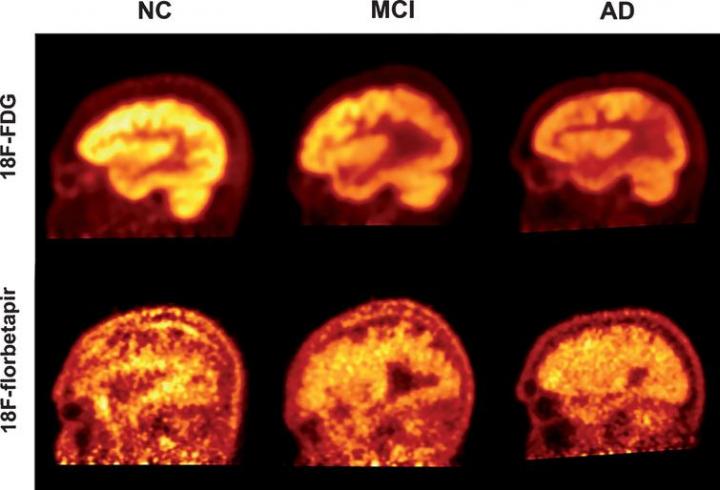

image: PET imaging using the radiotracers FDG and florbetapir to quantify cognitive decline in patients with Alzheimer's disease (AD), mild cognitive impairment (MCI), and healthy controls

Two of the most significant biomarkers found in Alzheimer's are decreased glucose uptake and the accumulation of amyloid plaques in the brain. PET scans use different radioactive drugs, called radiotracers, to measure these biomarkers within the brain tissue of patients with cognitive impairment. FDG-PET is one of the most commonly used imaging techniques to diagnose Alzheimer's. However, in recent years, several other radiotracers, such as florbetapir, have been developed to detect the deposition of amyloid plaques.

In this study, the researchers evaluated 63 individuals, including 19 with clinically diagnosed Alzheimer's disease, 23 with MCI, and 21 healthy individuals. The study participants underwent both FDG- and florbetapir-PET imaging. They were then assessed with a Mini Mental Status Examination (MMSE), a widely used diagnostic test for detecting and assessing the severity of cognitive impairment. The researchers used a novel "global quantification approach" to generate data from five different regions of the brain, which were correlated with the results from the MMSE scores.

The study revealed that both FDG- and florbetapir-PET scans are able to effectively discriminate the individuals with dementia from the healthy control group. However, when compared with the MMSE scores, the correlation between low cognitive performance and high levels of amyloid was significantly weaker than the correlation between FDG and low cognitive performance for all groups included in the study. This suggests that FDG-PET is a more sensitive indicator of cognitive decline.